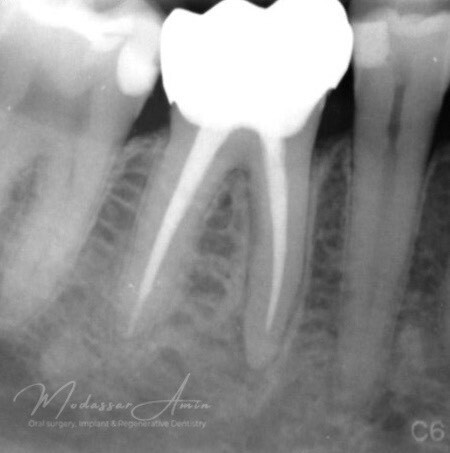

"Pasienten presenterte med tann 46 som ikke kunne bevares grunnet en dyptgående infraksjon inn i furkasjonen. Forholdene lå til rette for en immediate implantatbehandling. Ved hjelp av Versah osseodensifikasjonsbor ble det interradikulære beinet ekspandert på en skånsom og forutsigbar måte, noe som ga høy primærstabilitet (>40 Ncm) til tross for en lokal bendefekt apikalt mesialt etter kronisk apikal periodontitt. Den gode stabiliteten muliggjorde bruk av SSA (Sealing Socket Abutment) for forsegling. På grunn av tynn bløtvevsfenotype bukkalt ble behandlingen supplert med bindevevstransplantat (CTG)"

Kontrollröntgen för verifikation

Kontrollröntgen implantat